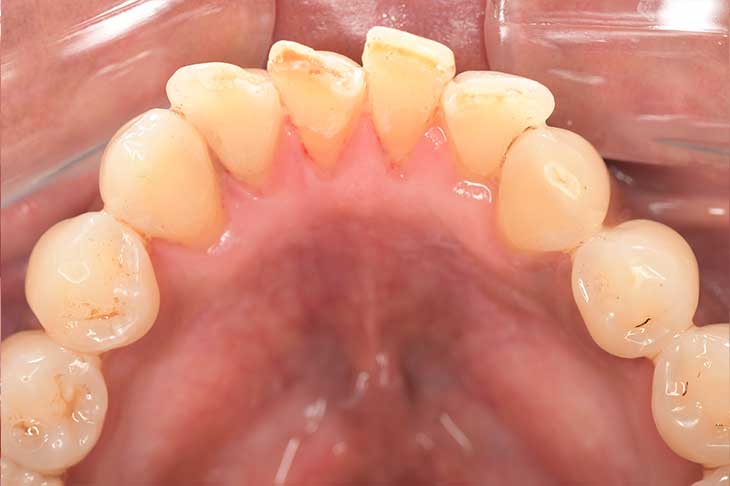

CASE 39

Before①

After①

Before②

After②

Before③

After③

基本情報

| 年齢・性別 | 90歳・男性 |

|---|---|

| 主訴 | 歯茎から血が出る |

| 治療部位 | 全顎 |

| 治療内容 | 1.歯ブラシでのTBI(歯磨き指導) 2.上顎のスケーリング、TBI(歯磨き指導) 3.下顎のスケーリング、歯間ブラシでのTBI(歯磨き指導) 4.PMTC(着色除去)、TBI(歯磨き指導) 4.再評価、TBI(歯磨き指導) 5.SRP(縁下歯石除去/4ブロックに分けて)、毎回TBI(歯磨き指導) 6.再評価 |

| 治療期間 | 2ヶ月間 |

| 治療費 | 合計:合計10,220円 ・内訳 スケーリング:640円 PMTC(着色除去):5,500円 上下顎のSRP(縁下歯石除去/左右):1,020円×4 (2022年12月現在) |

| リスク・副作用 | ・最初はブラッシング時、出血することがある。 ・スケーリング後、歯肉が下がり知覚過敏や、見た目上、歯が長く見えたり、隙間が開いてしまうことや、歯が揺れる可能性がある。 ・歯磨きを怠ると再度歯石が着く可能性がある。 |

| 治療方針 | 歯周病治療を行うにあたって、血圧の薬を他のものに変えて頂くか中断して頂かないと、この歯茎の盛り上がりは改善されないと判断し、患者様に相談し内科医より同意を得た上で、血圧の数値も安定していた為、無理ない範囲で中断してもらい、歯周病治療を行った。 治療期間中、特に問題なく、血圧の数値も安定していた。 歯周治療後は、内科医により血圧の薬の種類を変えて頂いた。 |

| 特記事項 | ・何十年も前に歯医者に行った時に虫歯もなく特に問題ないと言われ、それから一度も歯医者に通っておらず、自分では口腔内は健康だと思っていた。 ・血圧の薬(ニフェジピン:副作用で歯肉増殖を引き起こす薬)を服用していた為、歯茎が盛り上がってしまい清掃困難な状態だった。 |

| 担当者所見 | 歯周病治療を成功させるために一番重要なことは、ホームケアの確立であることを改めて実感した。 患者様自身、自分が歯周病だとは思っていなかったが、歯周病治療がひと段落した時に、「歯茎から出血しなくなり食事が美味しくなった」と今までの口腔内との違いを実感していた。 |